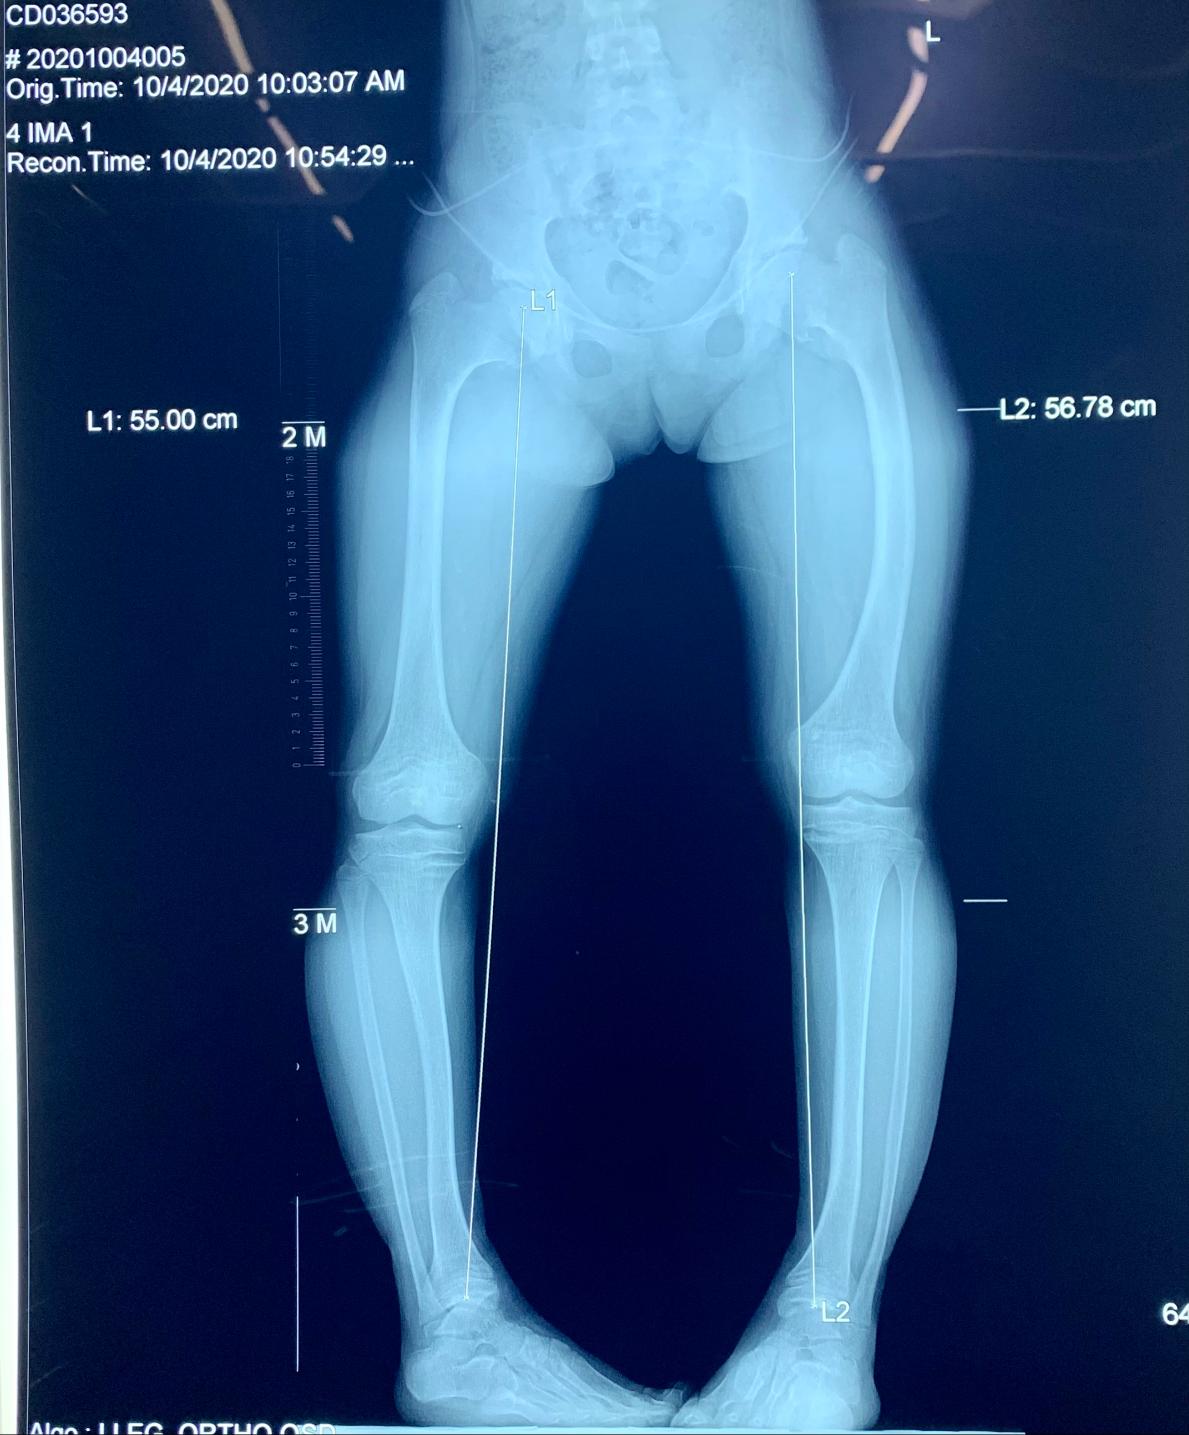

足外翻角度测量

运动发育落后的儿童足外翻角度往往是比较大的,即外翻都比较明显,且不能够自行缓解。这主要是由于孩子大运动发育落后,全身肌肉力量不足,韧带比较松弛。而足作为整个身体的负重单元,因此足部关节韧带无法承受载荷而表现最为明显。因此,家长们往往发现孩子的第一个问题就是足外翻。